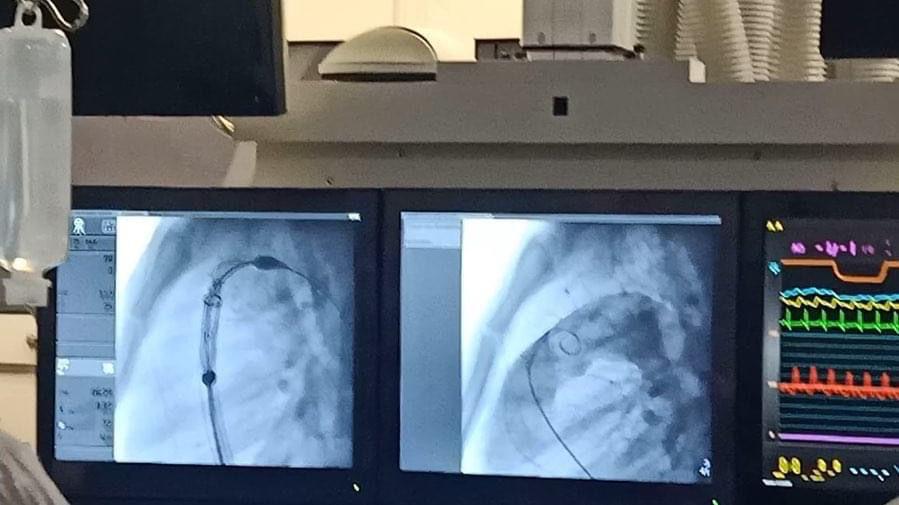

في سابقة هي الأولى من نوعها بمستشفيات جامعة عين شمس، تم بنجاح إجراء زراعة صمامات رئوية لثلاث حالات، عن طريق القسطرة، وفق تصريحات أ.د. عزة الفقي، أستاذ ورئيس قسم القلب بكلية الطب جامعة عين شمس.

من جانبها قالت أ.د. مي حمدي السيد أستاذ القلب ومؤسس وحدة عيوب القلب الخلقية بقسم القلب بطب جامعة عين شمس، أن تنفيذ هذه التقنية تم بالتعاون مع أ.د. زياد حجازى أستاذ زائر من الولايات المتحدة الأمريكية، لافتة أن تقنية الصمام الأورطي موجودة في مصر منذ سنوات ولكنها لأول مرة تنفذ في الصمامات الرئوية.